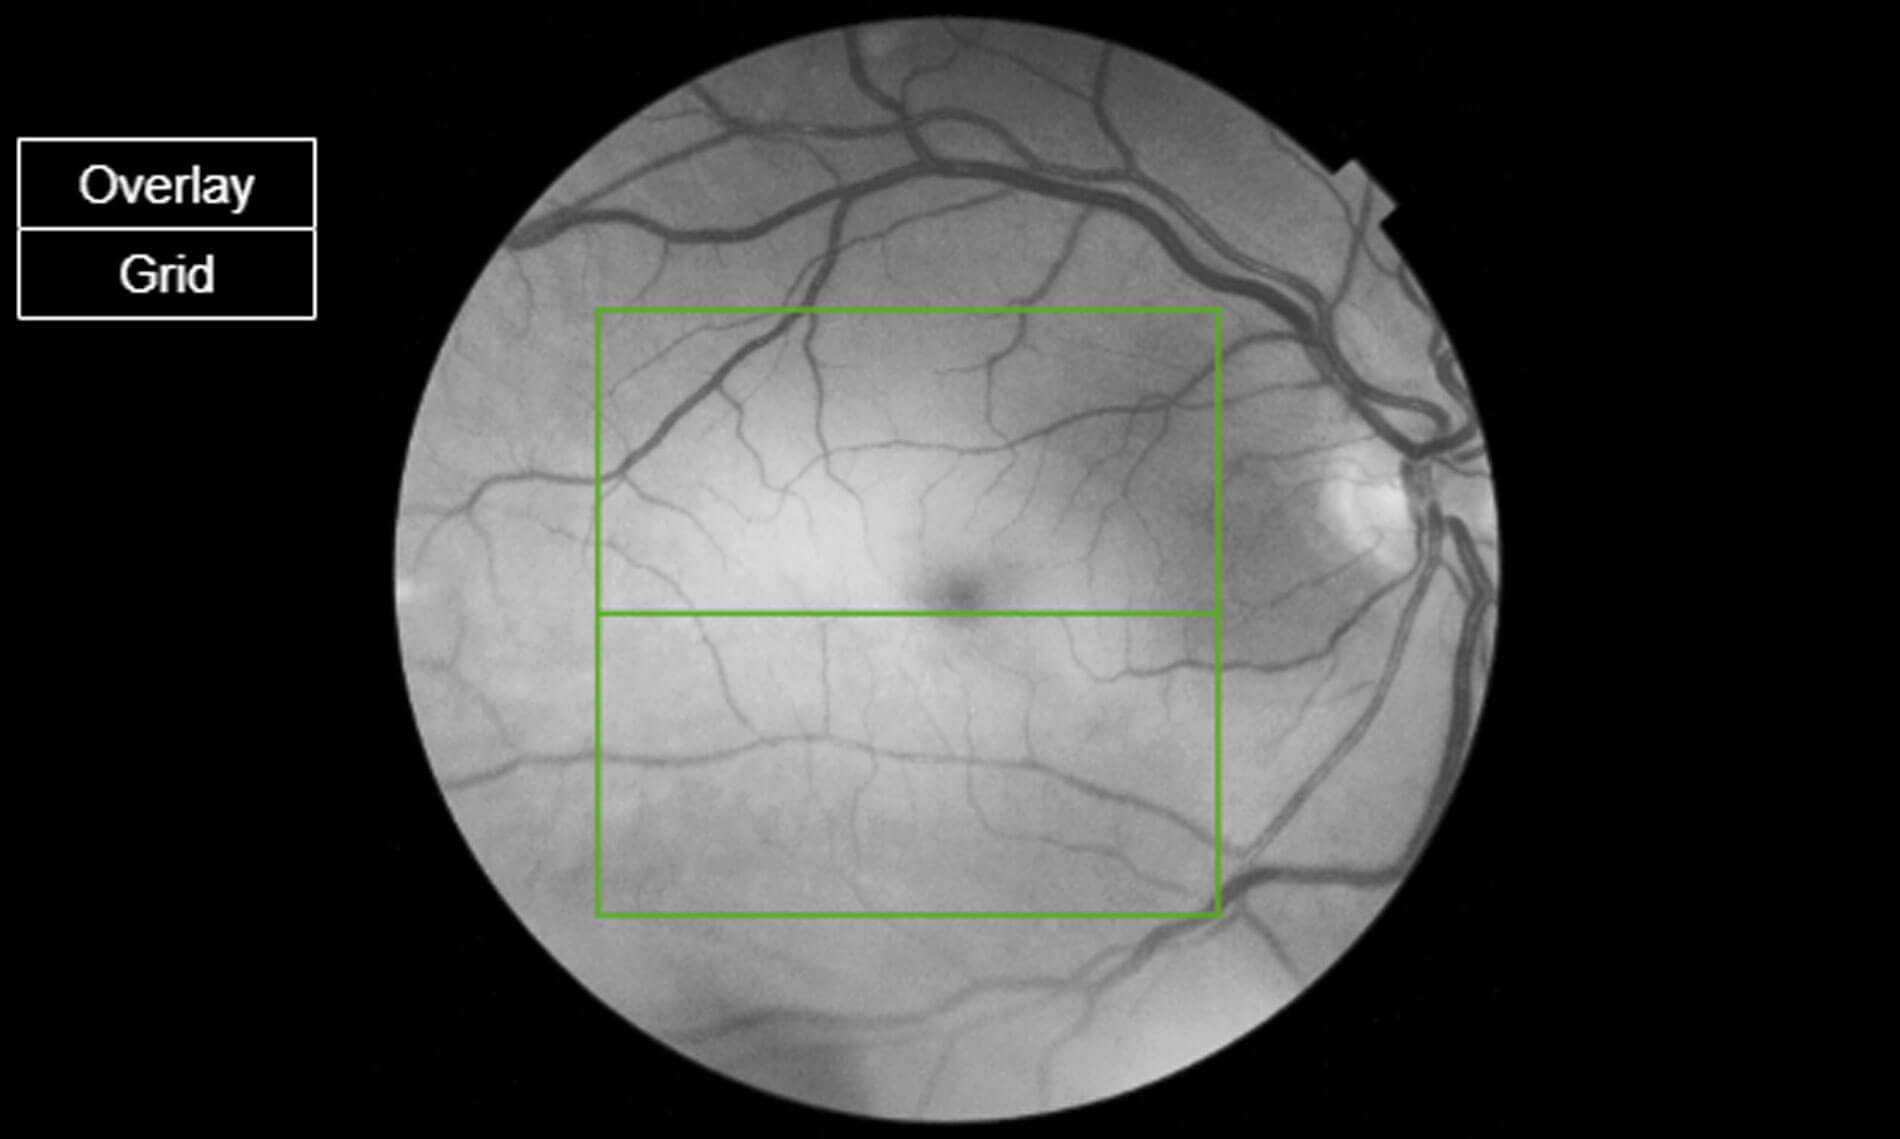

Figure 2: Image obtained on OCT scan showing right fundus an hour later showing significant improvement

in the retinal oedema (retinal reperfusion) and the large thrombus dislodged (arrow).

An hour after treatment the patient felt improvement of his visual acuity and reduction of the size of the scotoma he presented with. He had repeated fundoscopic examination and clinical imaging to check the position of the thrombus. The thrombus had dislodged as shown in Figure 2, and the retina had re-perfused (Figures 3 and 4). Visual acuity was rechecked as LogMAR 1.06 (6 metres). Blood tests were found to be normal and after discussion with the stroke team the patient was referred urgently to the stroke team and follow-up was planned in the medical retina clinic.

Figure 3: Red free image of the right macula showing ischaemic oedema (white bright signal).

Figure 4: Red free image of the right macula following reperfusion showing improvement

of the oedema and reduction of the abnormal signal.